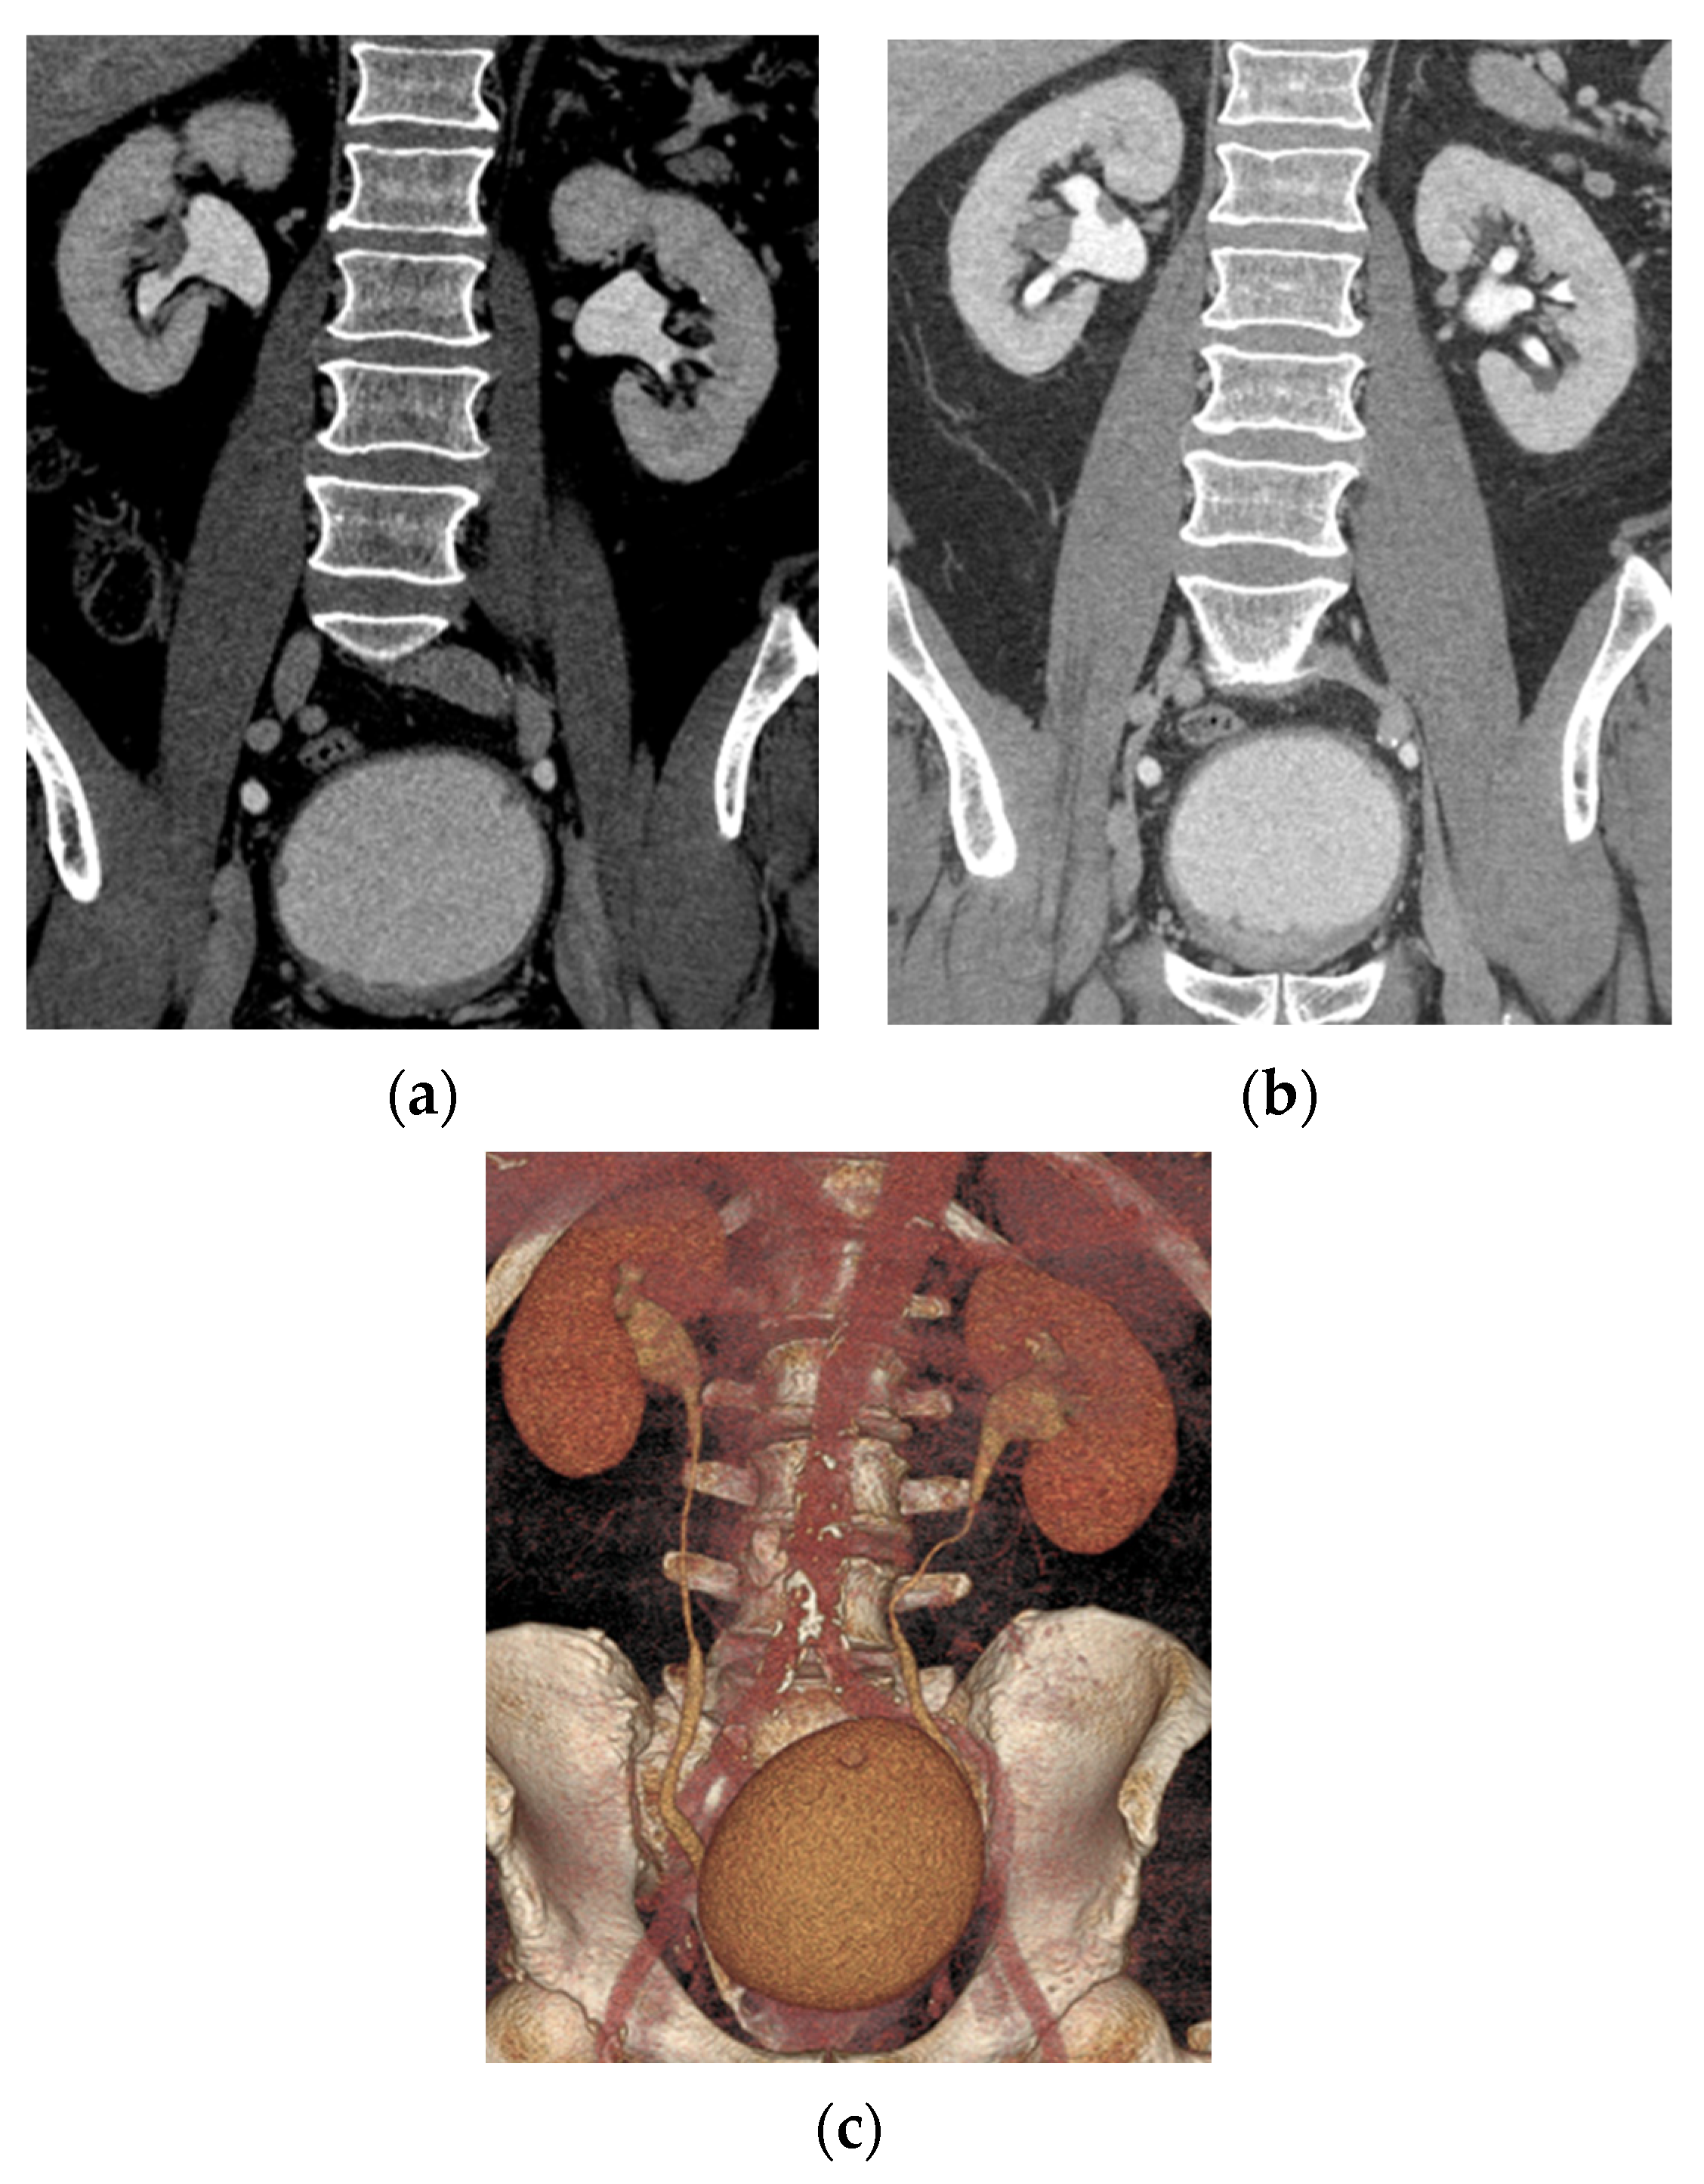

5.1. Computed Tomography (CT)